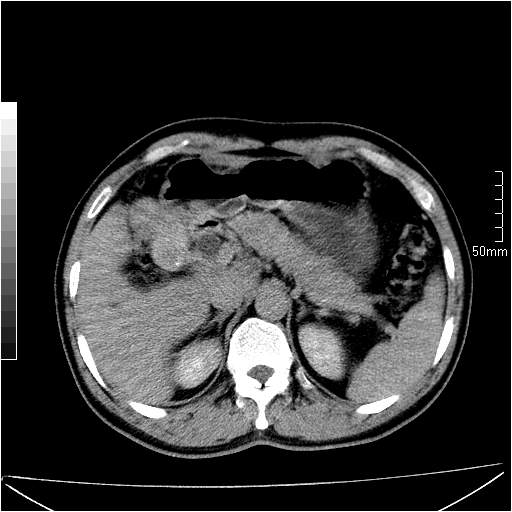

男性,54岁,皮肤黄染,搔痒一周余.b超示肝左叶回声异常.初步诊断1胆总管下段结石2胆囊结石伴慢性胆囊炎请各位战友帮忙看一下肝脏多发低密度如何解释恰当.增强效果不是很好.请大家见谅.

胆总管及肝内胆管扩张,考虑是结石!但,肝内的低密度区增强不明,可能是肝ca,因为肝ca在增强时呈快进快出.另年胆总管扩张原因,可以考虑一下是不是,胆管ca.再次要考虑肝内的低密度是否为海绵状血管瘤所致!

首先,胆总管下端结石梗阻伴肝内胆管扩张可确定。

其次,增强动脉期肝静脉显影,肝实质密度不均。——此为右心功能不全引起肝淤血的表现。

另外,肝八段低密度占位,呈多灶性,考虑肝脓肿或肝癌可能,(图像质量欠佳)建议进一步检查。

既然做了增强,为什么光提供延时期片子,肝动静脉期肝右叶前下段病灶增强如何?另外胆囊壁增厚,欠规整,内密度不均,与肝右叶病灶分界不清,增强表现怎样?肝内胆管轻度扩张,胆总管扩张,但未见明显结石影,也应提供增强早期图像才好鉴别扩张原因。片子较清,但不够完整,暂考虑1.胆囊癌肝局部浸润,或肝癌胆囊侵犯,2.胆总管下端或胰头钩突部占位。总之本人看不明白,请高手画图指示,先谢了!

由于胆囊窝内结构显示不清,肝脏病灶又邻近胆囊窝首先考虑胆囊癌肝受侵犯。而后因肝脏病灶强化有渐进改变,且相邻胆管扩张,故考虑肝胆管细胞癌待排。

左肝胆管细胞癌。

胆总管下端结石。